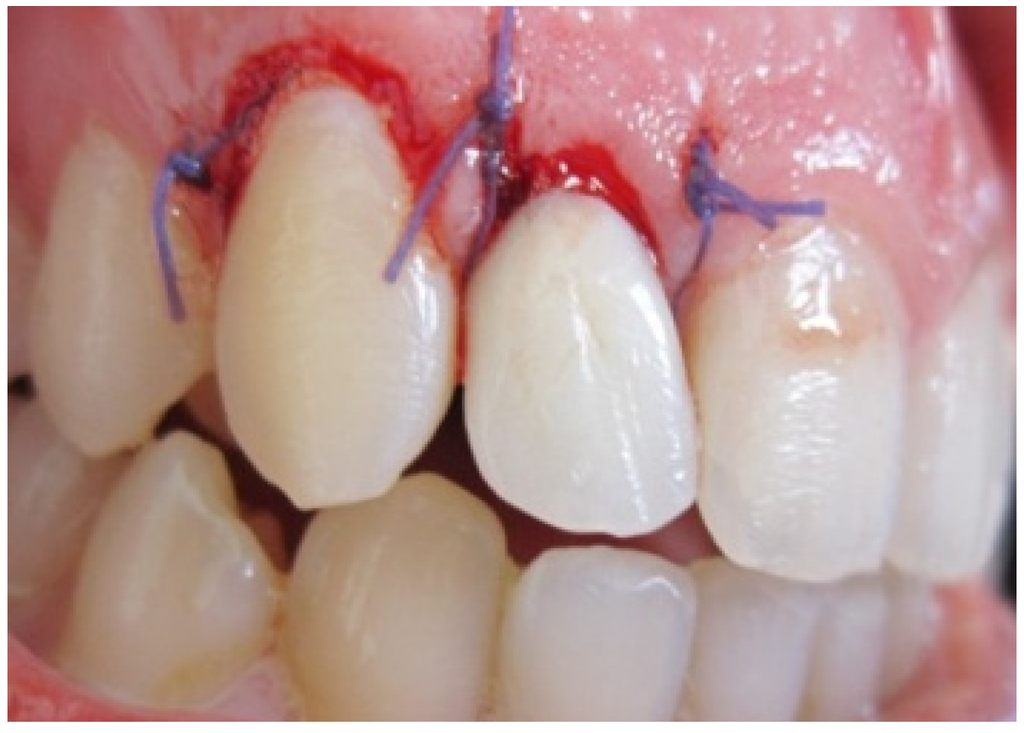

Provisional restoration was relined and modified within the refined preparation according to new gingival margins. It was cemented with non Eugenol Temporary Cement (Figure 5) which would guide the healing process.

Figure 5. Temporization.